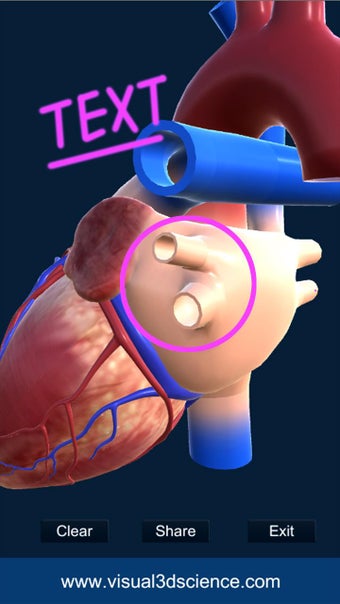

Puedes seleccionar la vista de rayos X, ocultar y mostrar partes del corazón, así como ver animaciones en tiempo real, dibujar o escribir en la pantalla y compartir capturas de pantalla, pronunciación de audio para todos los términos de anatomía y más.